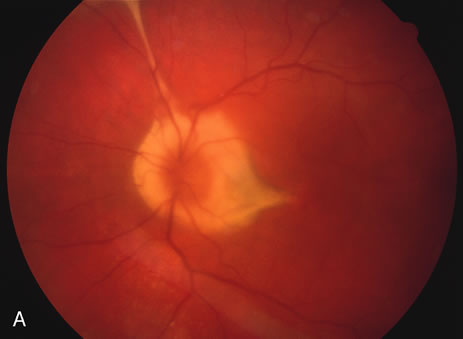

The classic findings in the acute cases are lesions of variable size that are hypofluorescent in the early phase of the fluorescein angiogram. In the late phases of the angiogram there is hyperfluorescence of the lesions. In the late phases, there also may be leakage from the disc as well, and there also may be staining of the retinal vessels because of the vasculitis. With resolution of the disease, there still may be a mottled pattern of fluorescence correlating with the areas of pigment clumping and pigment atrophy (Fig. 8).

Fig. 8. A. Early fundus angiogram showing hypofluorescence of the acute posterior multifocal placoid pigment epitheliopathy (APMPPE) lesions. B. Later stage of the angiogram showing staining of the APMPPE lesions.